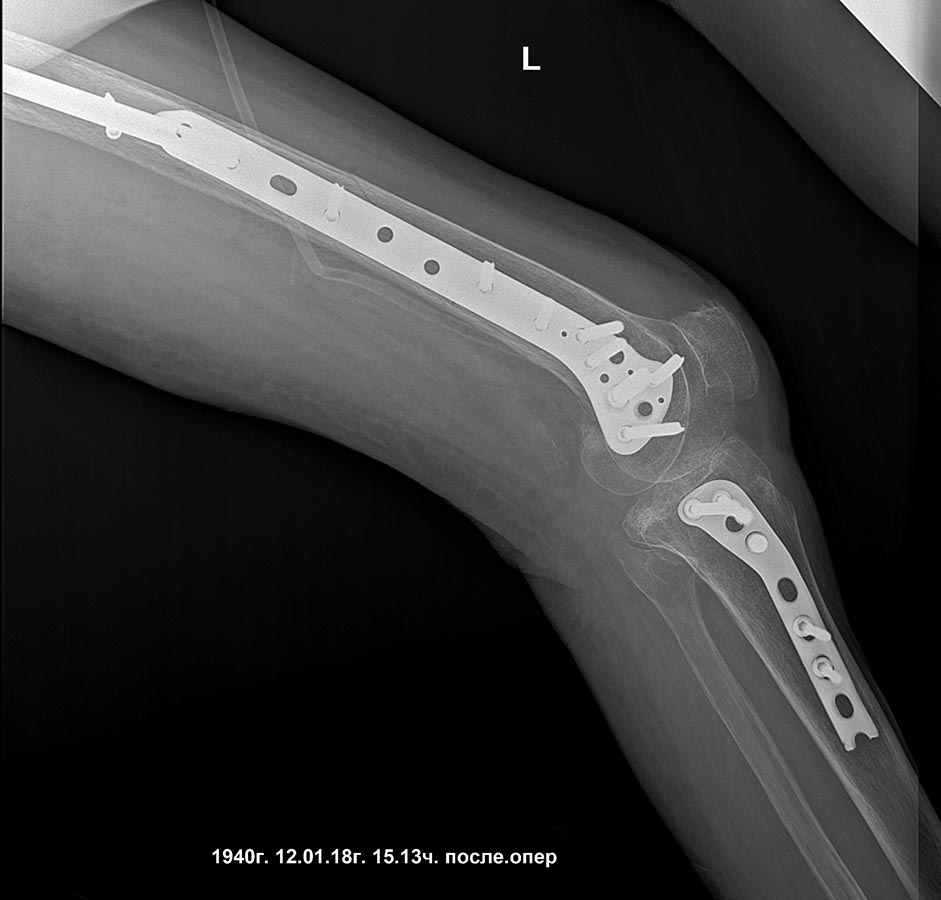

Нижняя треть - - это про диафиз. А тут, похоже, перелом наружного мыщелка бедра. Да, одним гвоздем тут тогда не стоит пытаться. Это две разные проблемы. Дейстительно, для дистального перелома подойдет соответствующая пластина. А в проксимальном отделе - короткий PFN после вальгизации.

добрый день! вроде все получилось сделать,закрыто,чрезкожная остеотомия. дистальная пластина тоже малоинвазивно

мыщелки

боковая